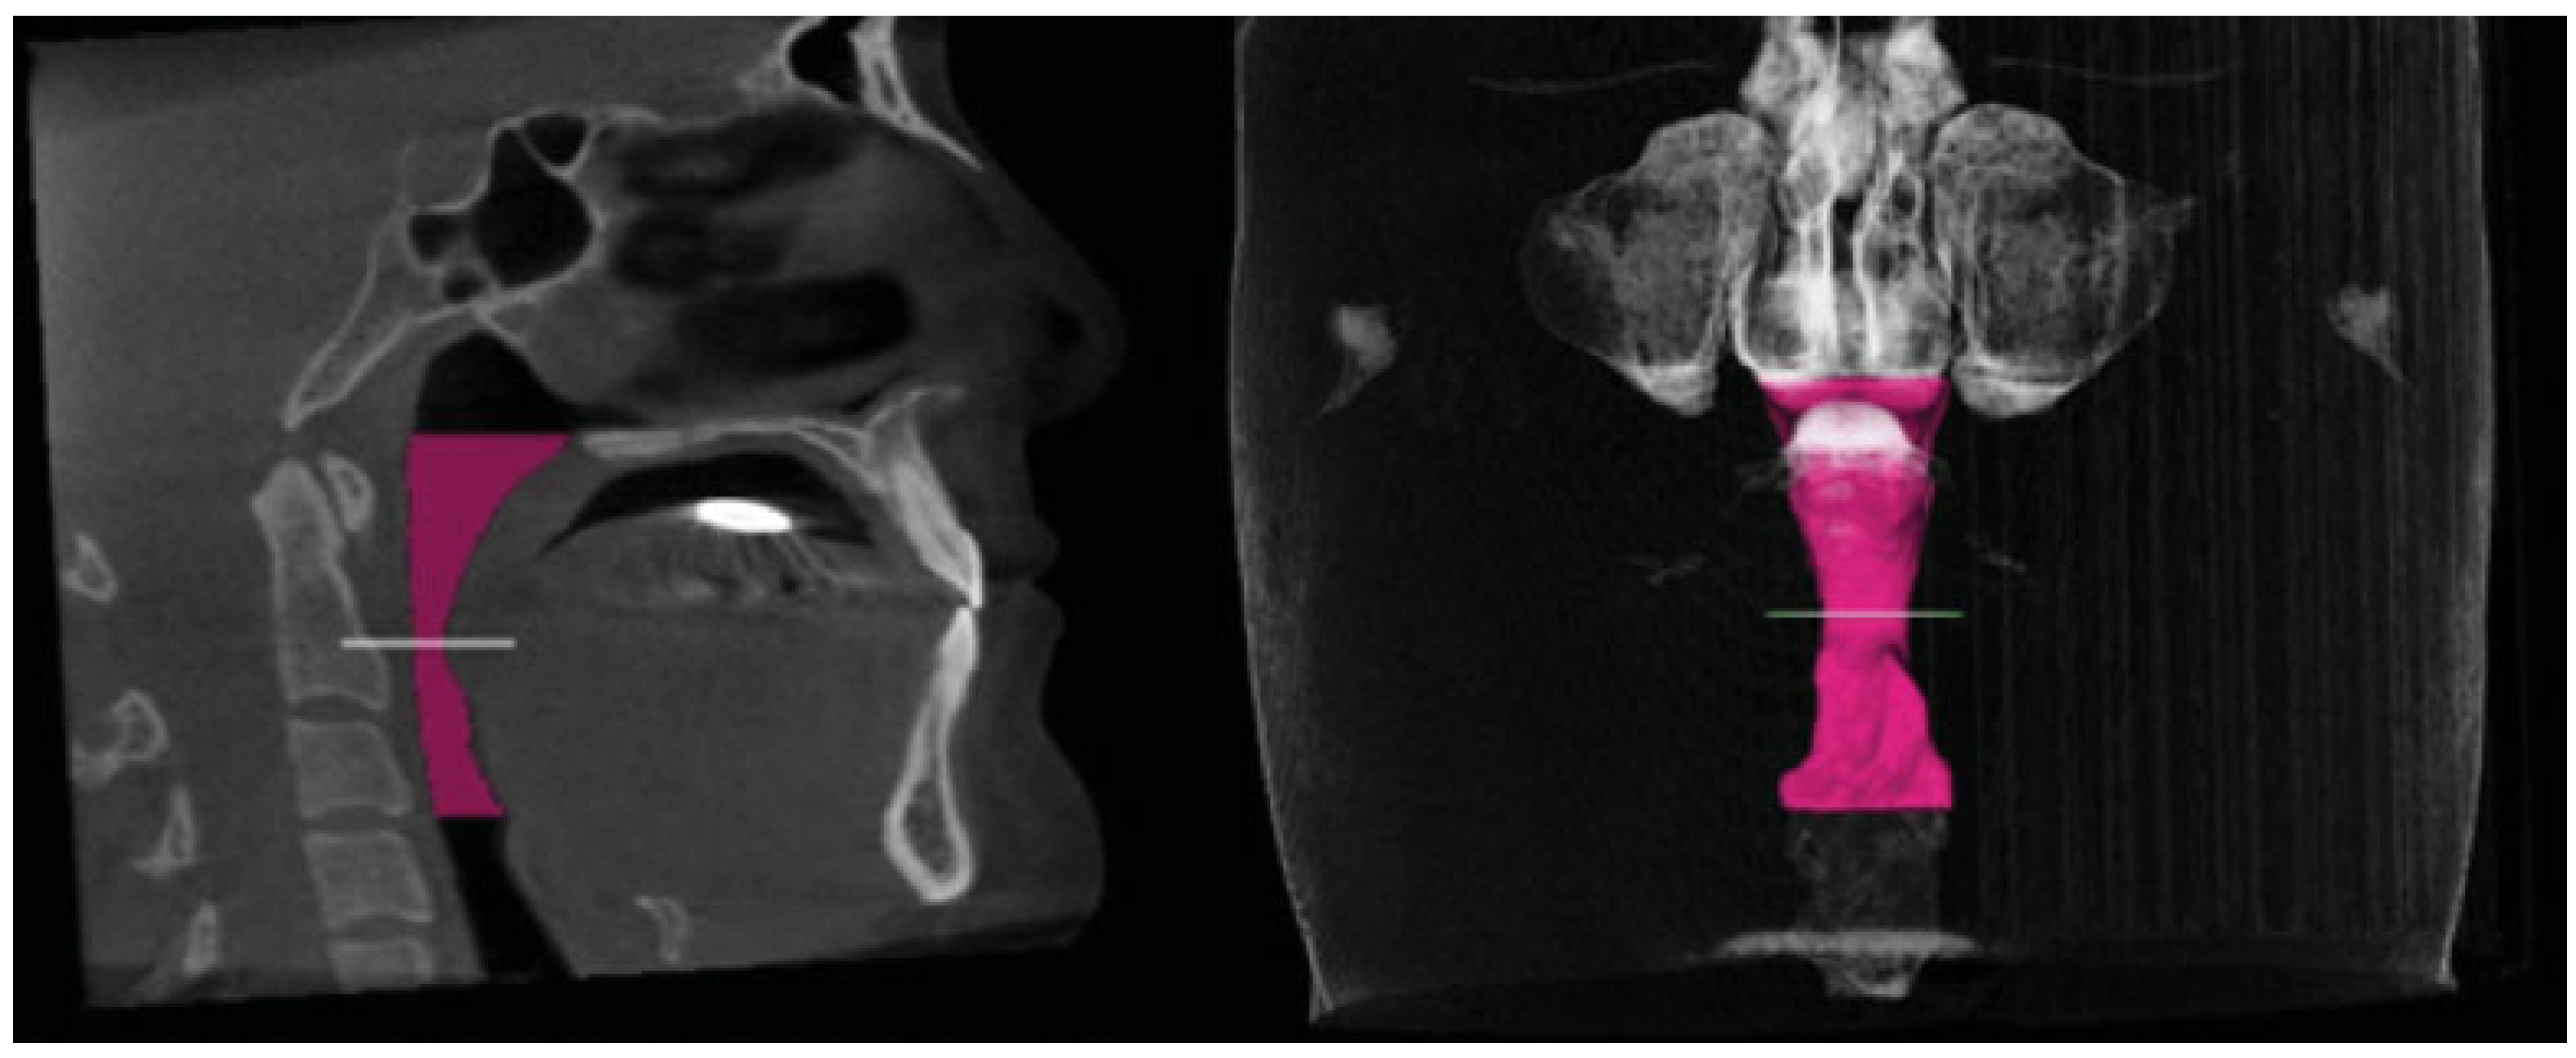

Comparison of Imaging Softwares for Upper Airway Evaluation: Preliminary Study

:Materials and Methods

Results